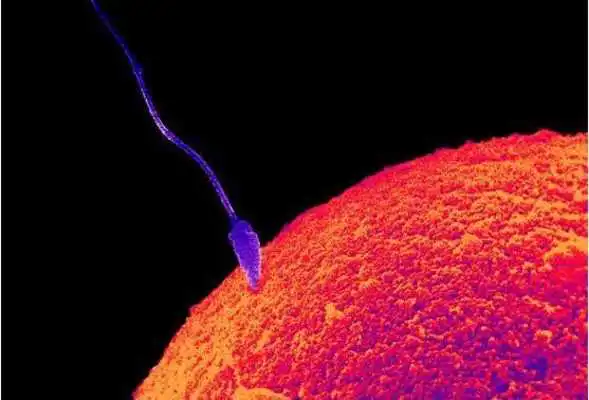

Tips ibu hamil app merupakan Informasi mengenai perkembangan janin dalam kandungan yang dirangkum berdasarkan periode Kehamilan, mulai dari Kehamilan minggu ke 1 sampai minggu ke 42.Pada Aplikasi ini dibahas tuntas mengenai tata cara dan keluhan yang sering dirasakan oleh ibu hamil pada umumnya dan bagaimana proses pembentukan janin mulai dari proses pembuahan sel telur sampai terciptanya sang bayi dimuka bumi ini.